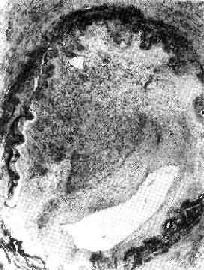

图3-6 机化的血栓

血管腔内的血栓已为肉芽组织取代有再通现象